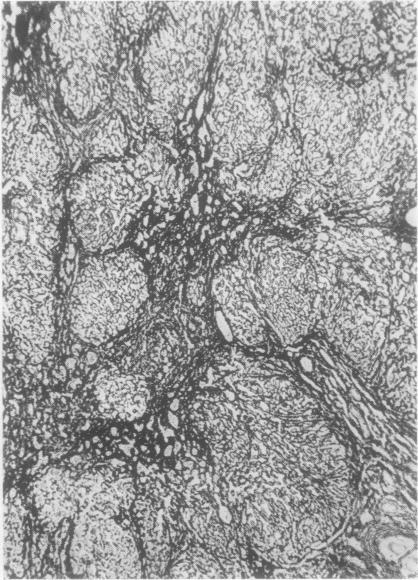

Obstruction of inferior vena cava by a persistent eustachian valve in a young adult.

J Clin Pathol. 1957 Feb;10(1):40-5. doi: 10.1136/jcp.10.1.40.